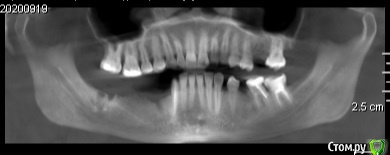

Екатерина Ч. Опубликовано 10 октября, 2020 Поделиться Опубликовано 10 октября, 2020 Здравствуйте. Хочу сделать имплантацию зубов. Нужно ли будет наращивать костную ткань Ссылка на комментарий

Nazim_NV86 Опубликовано 10 октября, 2020 Поделиться Опубликовано 10 октября, 2020 (изменено) Здравствуйте. Срезы(сечения) нужны и желательно с измерениями. Даже просто вертикально и горизонтально по 5мм нарисовать чтоб масштабы были понятны. Изменено 10 октября, 2020 пользователем Nazim_NV86 1 Ссылка на комментарий